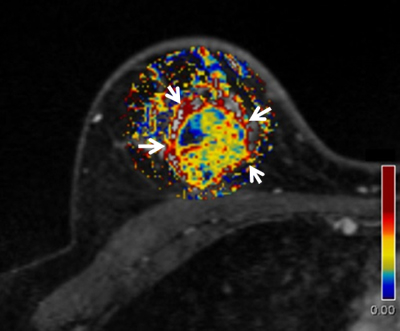

トリプルネガティブ乳癌のダイナミックMRI。

ダイナミックMRIの解析よって算出されたve値(間質の容積を表す)のパラメトリックマップである。腫瘍の辺縁周囲は高いを示し(赤領域、矢印)、腫瘍内はve値の低い領域(青領域)が混在している。